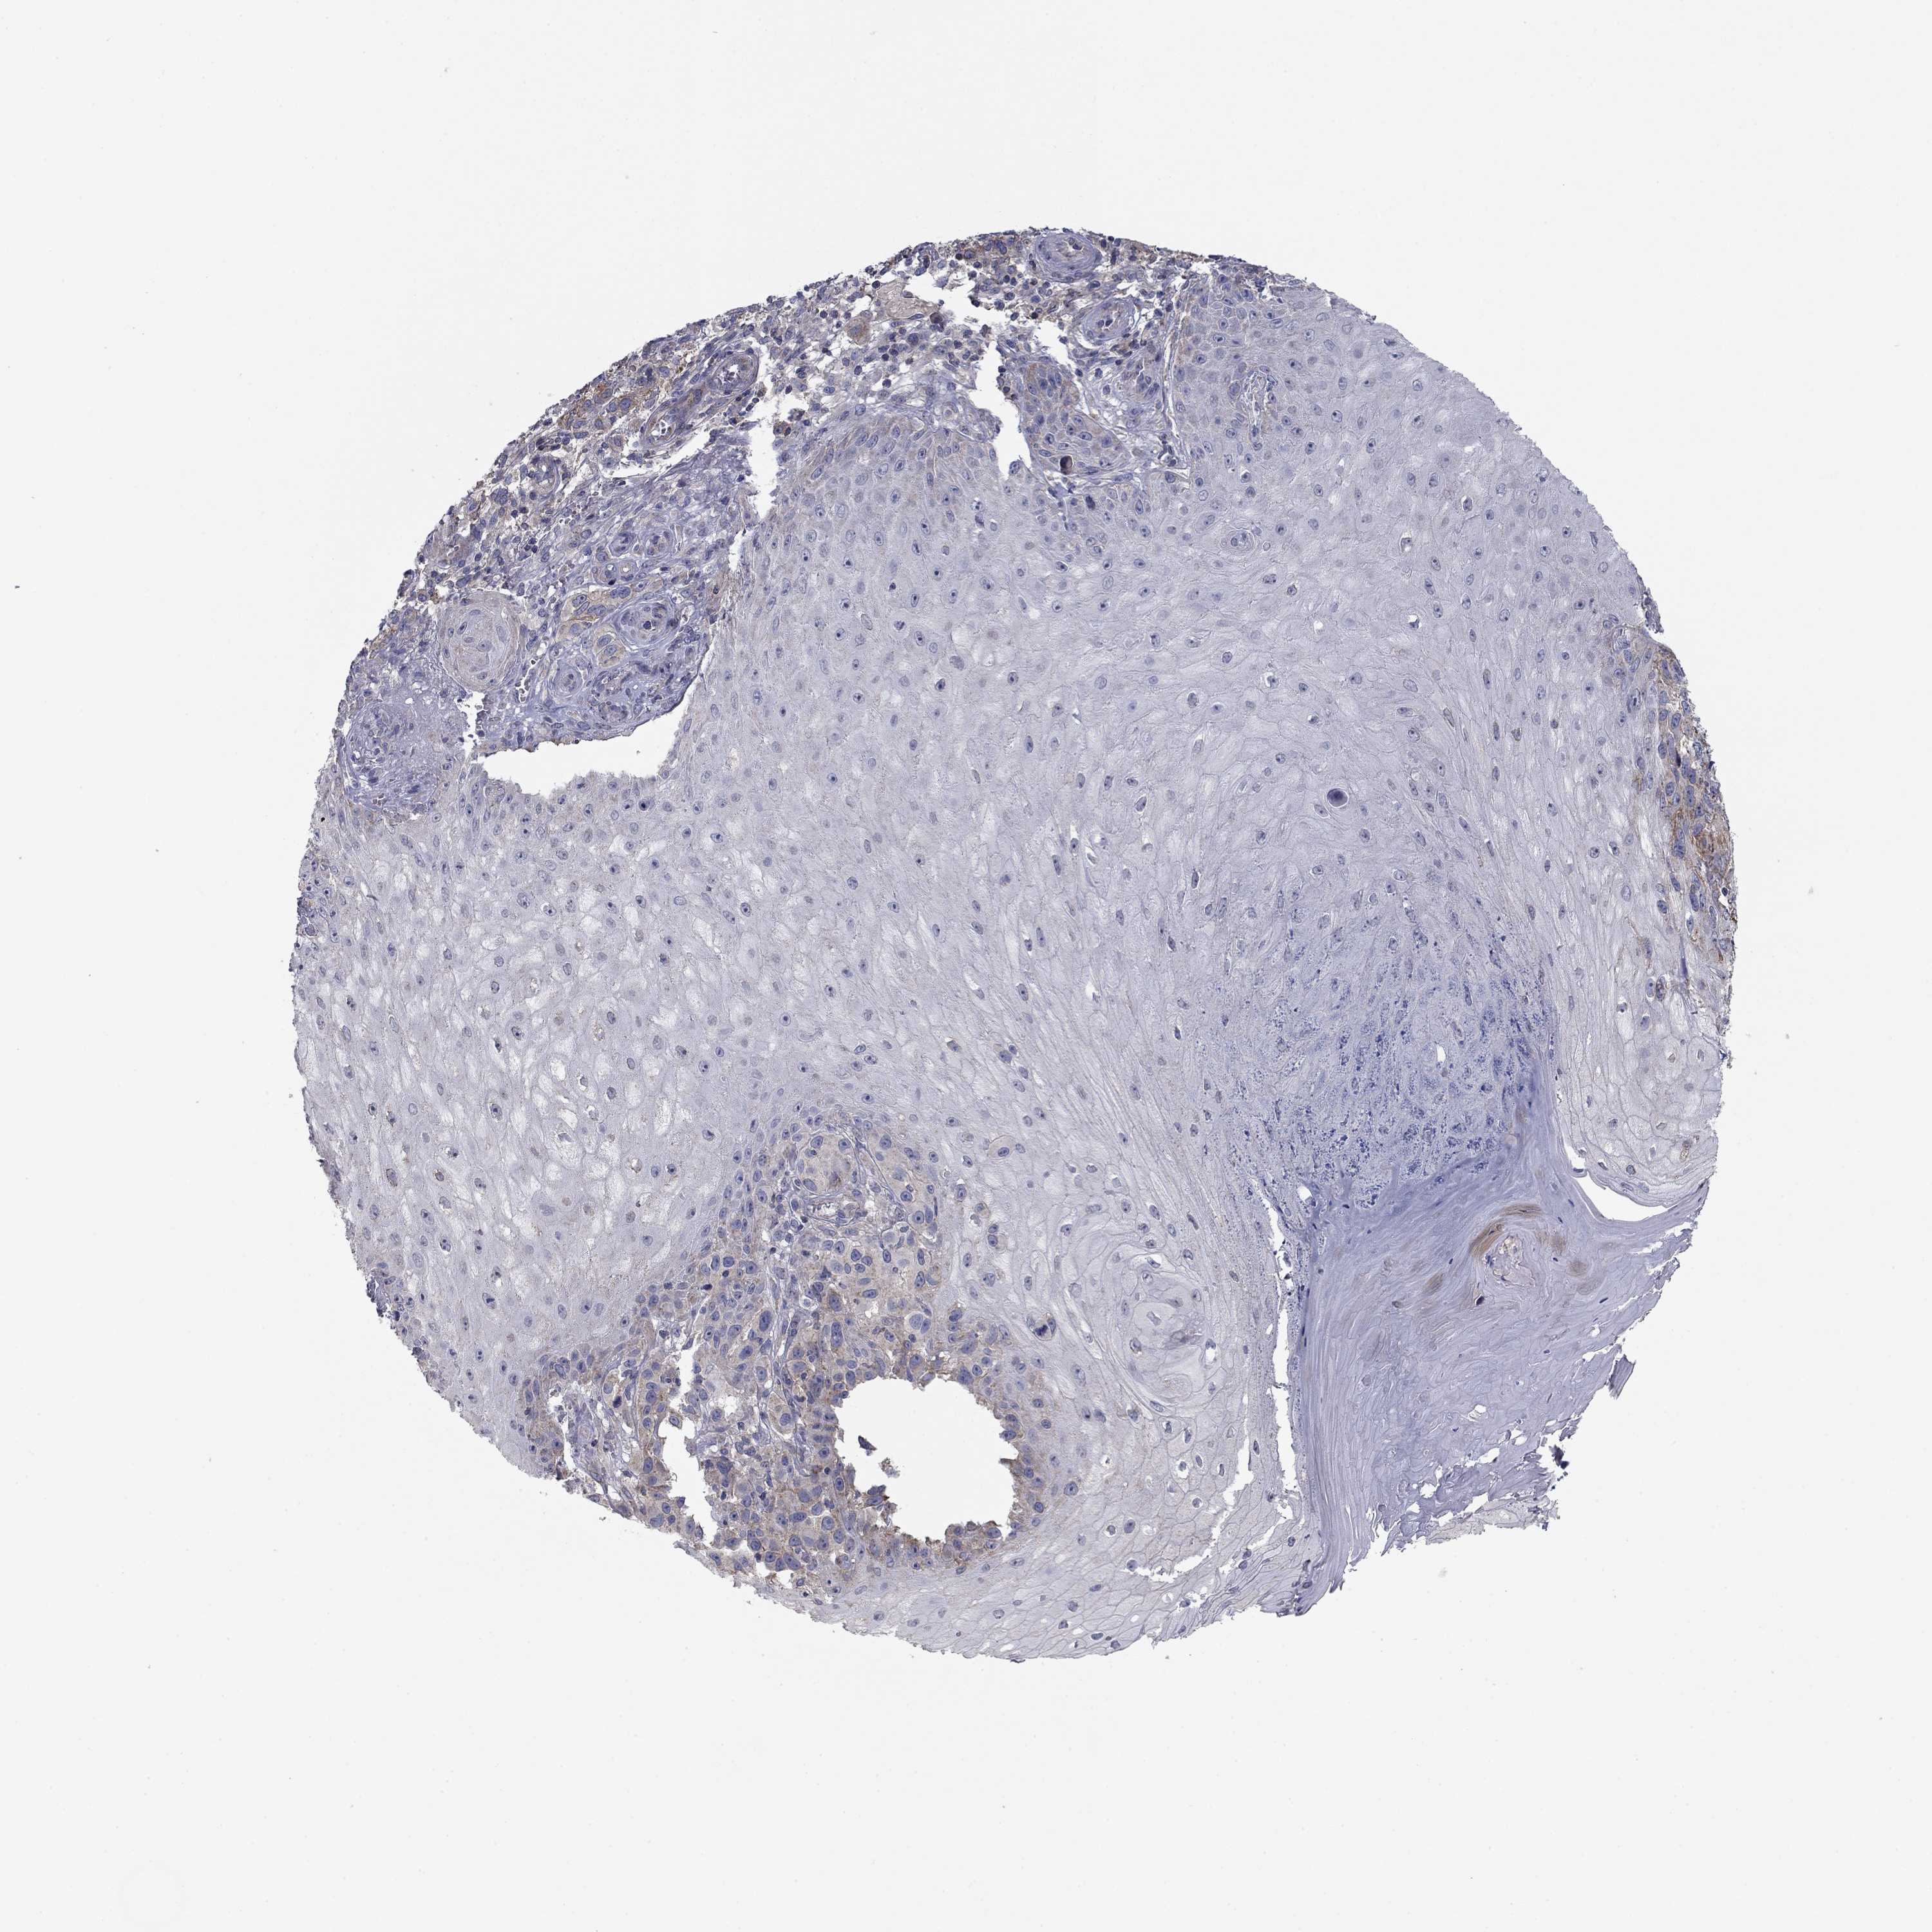

MELANOMA - Protein expressioni

A mouse-over function shows sample information and annotation data. Click on an image to view it in a full screen mode. Samples can be filtered based on level of antibody staining by selecting one or several of the following categories: high, medium, low and not detected. The assay and annotation is described here.

Note that samples used for immunohistochemistry by the Human Protein Atlas do not correspond to samples in the TCGA dataset.

Antibody stainingi

Antibody staining in the annotated cell types in the current human tissue is reported as not detected, low, medium, or high, based on conventional immunohistochemistry profiling in selected tissues. This score is based on the combination of the staining intensity and fraction of stained cells.

Each image is clickable and will lead to virtual microscopy that enables deeper exploration of all samples and also displays staining intensity scores, fraction scores and subcellular localization as well as patient and tissue information for each sample.

Antibody HPA003548

Antibody CAB017633

Staining

High

Medium

Low

Not detected

Intensity

Strong

Moderate

Weak

Negative

Quantity

>75%

75%-25%

<25%

None

Location

Nuclear

Cytoplasmic/membranous

Cytoplasmic/membranous,nuclear

Malignant melanoma, NOS

Malignant melanoma, Metastatic site